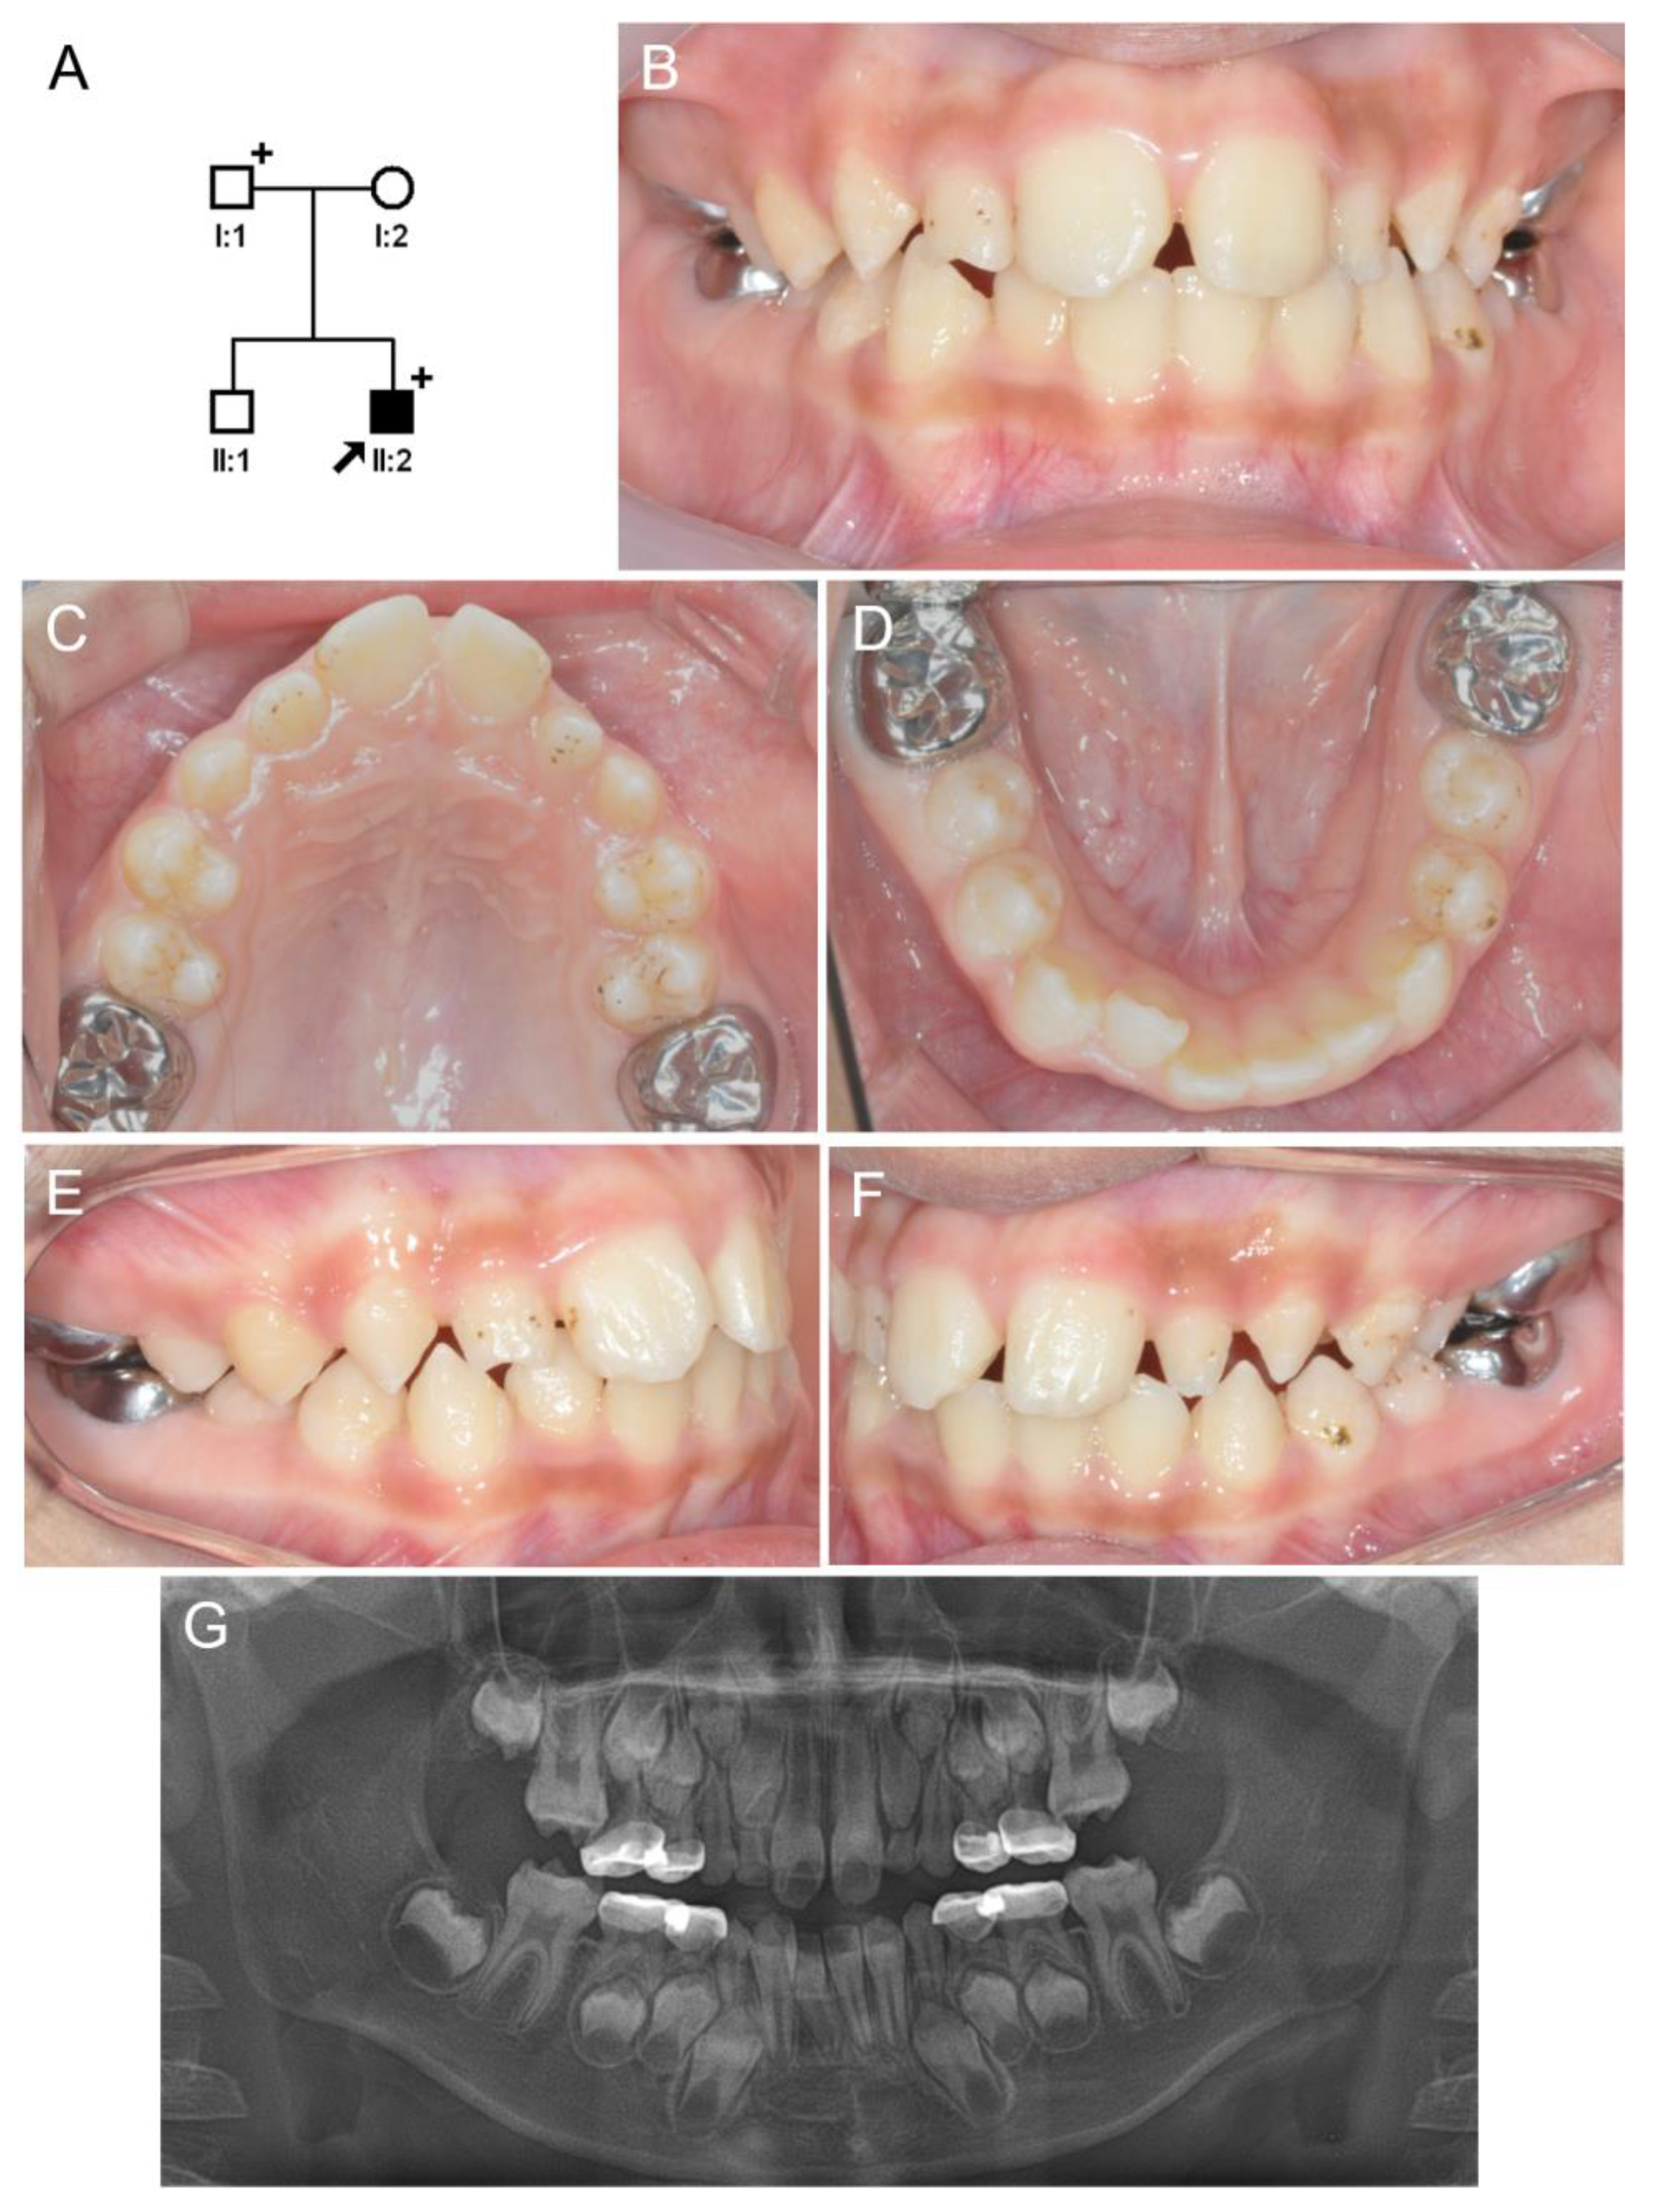

3.1. Family 1